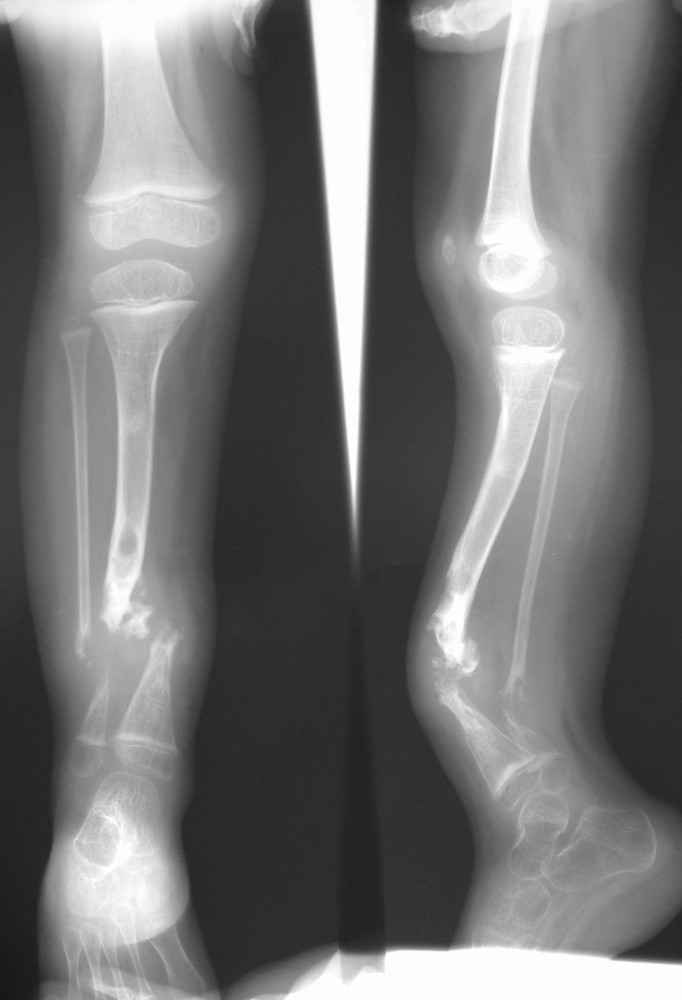

Уважаемые коллеги!Девочка, 2004 г.р.Родилась от I беременности, протекавшей с анемией и

носительством УПМФ, роды I срочные, осложненные.

Дз: Врожденная аномалия правой голени, врожденный ложный сустав,

врожденная дисплазия тазобедренных суставов, coxa valga.

Нейрофиброматоз, факоматоз.

В 2006 г. – остеоклазия с иммобилизацией циркулярной гипосовой

повязкой, в 2007 – интерлок, затем - костная аутопластика, стержневой АВФ.

С 2006 г. определена мышечная дистония.В 2008 г. впервые со слов родителей установлен диагноз

нейрофиброматоз. На МРТ - факоматоз. Поверхностная ЭМГ от 18.09.2008. - полученные

параметры характерны для миопатического синдрома.

Вопрос: какие возможны варианты лечения с учетом тяжелой

сопутствующей патологии (нейрофиброматоза)?Заранее благодарю!